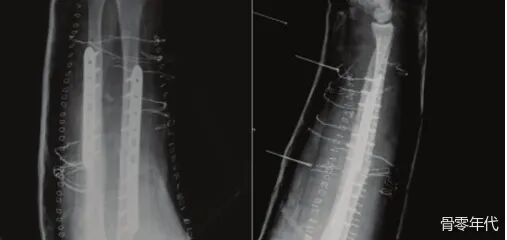

影像学表现